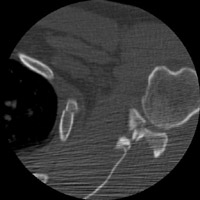

- Click on the image for a larger versionAAP chest radiograph. This demonstrates multiple left lateral rib fractures. The patient sustained a pneumothorax as well and a chest tube was placed.